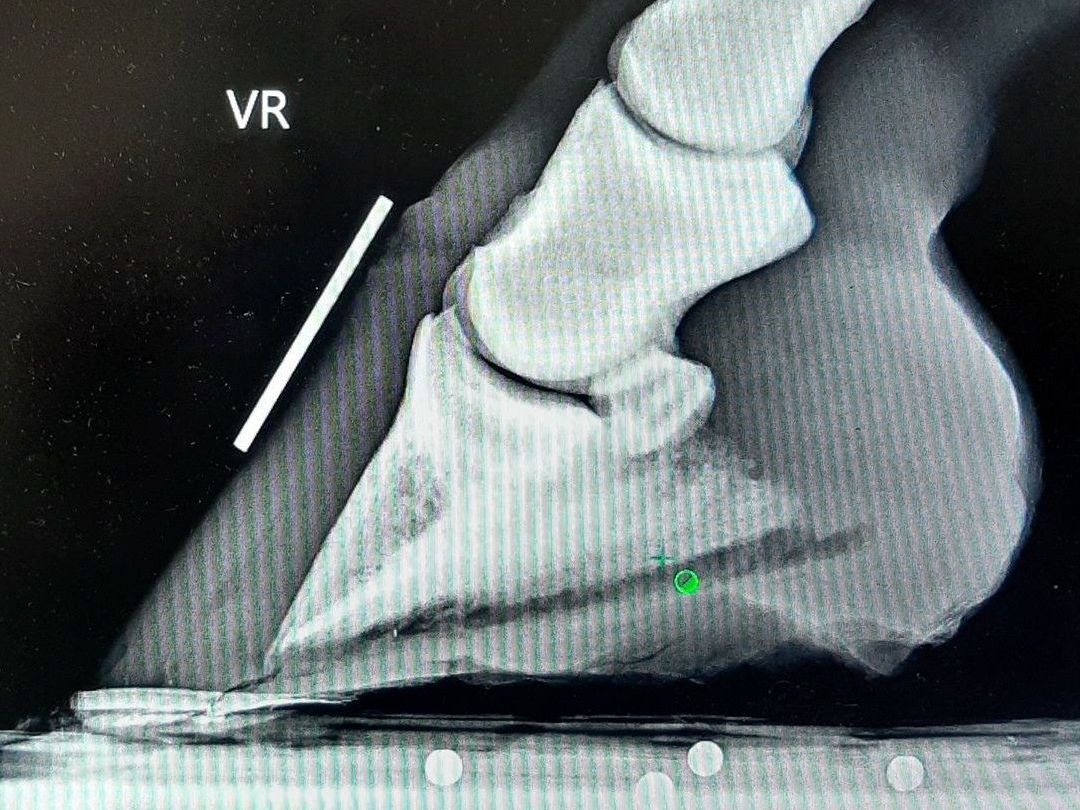

Hier benutze ich einen Holzclog, um die TBS zu entlasten und damit die Ziehkraft auf das Hufbein. Der Cast wirkt beim Nichtfunktionieren des Hufbeinträgers als Unterstützung der Hufwand.